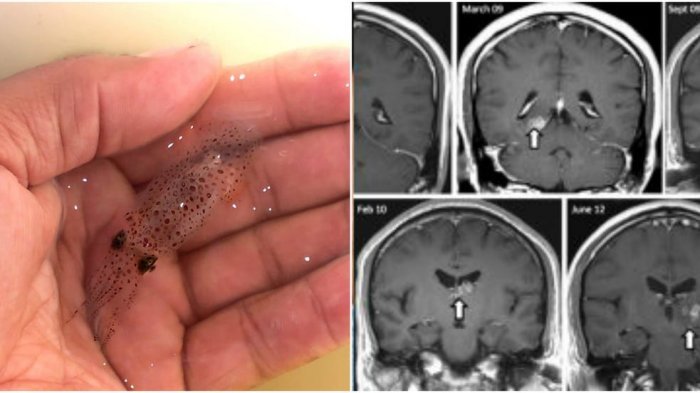

1. Cacing pita di otak

Luis Ortiz berusia 26 tahun segera dibawa ke ruang gawat darurat karena mengalami sakit kepala parah dan mual.

Saat dioperasi dokter menemukan sesuatu yang mengerikan dimana ada beberapa cacing pita yang hidup di kepala si pria.

Cacing pita yang biasanya berada di bagian organ pencernaan justru terperangkap di otak.